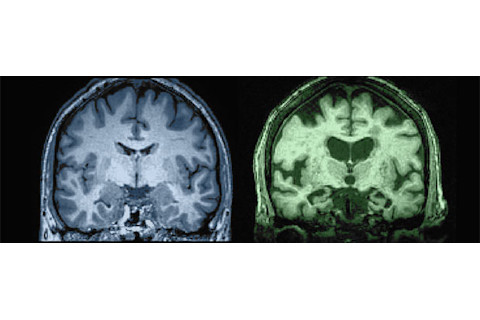

扫描图的故事:衰退中的大脑

大脑会随着年龄的增长而萎缩,导致各种各样的缺陷。俄勒冈健康与科学大学的神经科学家杰弗里·凯利用核磁共振扫描(如下图所示)来追踪这一过程。他说,萎缩发生在血流量减慢时,减少了大脑细胞可用的氧气和营养物质。这导致滋养和修复神经元的能力下降,并伴随认知能力下降。——艾玛·布莱斯

蛛网膜下腔 左图:27岁大脑 头骨与大脑之间的空间在年轻时紧密。 右图:87岁大脑 神经元网络萎缩,空间变宽,心理处理速度减慢。

脑室 左图:27岁 充满脑脊液的脑室缓冲大脑;年轻时它们狭窄。 右图:87岁 脑室随灰质萎缩而扩大;执行功能下降。

白质束 左图:27岁 由神经纤维和神经胶质细胞组成的神经通路高效传输信号。 右图:87岁 神经胶质细胞随年龄萎缩,扰乱信号传输并导致认知能力下降。所有图片均由俄勒冈大脑衰老研究中心、波特兰退伍军人医疗中心和俄勒冈健康与科学大学提供。 一些大脑如何保持敏锐